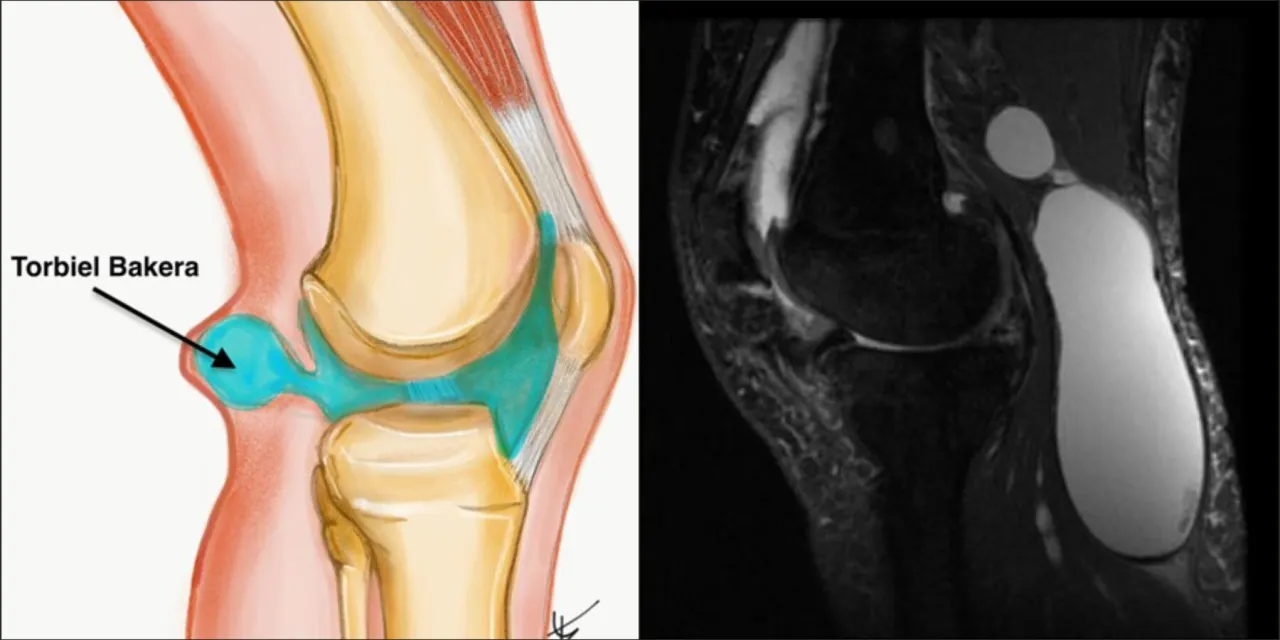

Torbiel Bakera, znana również jako cysta Bakera, to wypełniony płynem guzek, który pojawia się w dole podkolanowym. Choć często bywa źródłem dyskomfortu i bólu, rzadko stanowi problem pierwotny. Zazwyczaj jest sygnałem, że w stawie kolanowym dzieje się coś więcej na przykład rozwija się choroba zwyrodnieniowa, reumatoidalne zapalenie stawów (RZS) lub doszło do uszkodzenia łąkotki. Właśnie dlatego tak ważne jest zrozumienie, jak farmakologiczne metody leczenia mogą przynieść ulgę w objawach, jednocześnie pamiętając, że kluczem do trwałego rozwiązania problemu jest zajęcie się jego pierwotną przyczyną.

Torbiel Bakera to nic innego jak wypełniony płynem guzek, który tworzy się w dole podkolanowym, czyli za kolanem. Powstaje, gdy nadmiar płynu stawowego, wytwarzanego w kolanie w odpowiedzi na stan zapalny lub uszkodzenie, przedostaje się do kaletki maziowej znajdującej się w tej okolicy. Ważne jest, aby zrozumieć, że torbiel Bakera jest zazwyczaj problemem wtórnym. Oznacza to, że jest ona konsekwencją innej, pierwotnej dolegliwości stawu kolanowego, takiej jak choroba zwyrodnieniowa, reumatoidalne zapalenie stawów (RZS) czy uszkodzenia łąkotek. To właśnie te schorzenia prowadzą do zwiększonej produkcji płynu stawowego. Dlatego, choć leczenie farmakologiczne jest niezwykle ważne w łagodzeniu objawów, samo łykanie tabletek nie usunie torbieli na stałe, jeśli nie zajmiemy się jej główną przyczyną.